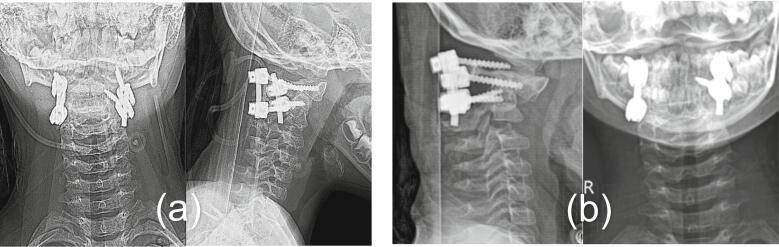

We present two cases of Os odontoideum accompanied by Down syndrome. Both patients were hospitalized due to progressive tetraparesis after falls several months prior. Upon examination, the patients exhibited myelopathy and were unable to walk or stand. MRI revealed spinal stenosis at the C1-C2 level due to atlantoaxial dislocation. C1-C2 fixation using Harms' technique was performed in both cases. One case experienced a complication involving instrument failure, necessitating revision surgery.

Due to the characteristics of transverse ligament laxity, low muscle tone, excessive joint flexibility, and cognitive impairment, children with both Down syndrome and Os odontoideum are at a high risk of disability and even mortality from spinal cord injury. Most authors recommend surgical management when patients exhibit atlantoaxial instability. Additional factors such as low bone density, cognitive impairment, and a high head-to-body ratio may increase the risk of surgical instrument failure and nonunion postoperatively in patients with Down syndrome.

我们报告两例伴有唐氏综合征的齿突缺如病例。两名患者均因数月前跌倒后进行性四肢轻瘫入院。检查时,患者表现出脊髓病,无法行走或站立。MRI显示由于寰枢椎脱位,C1-C2水平存在椎管狭窄。两例均采用哈姆斯(Harms)技术进行C1-C2固定。其中一例出现器械故障并发症,需要进行翻修手术。

由于唐氏综合征患儿存在横韧带松弛、肌张力低、关节过度灵活以及认知障碍等特点,患有唐氏综合征和齿突缺如的儿童因脊髓损伤导致残疾甚至死亡的风险很高。大多数作者建议,当患者出现寰枢椎不稳时应进行手术治疗。其他因素,如骨密度低、认知障碍和头身比例高,可能会增加唐氏综合征患者术后手术器械故障和不愈合的风险。